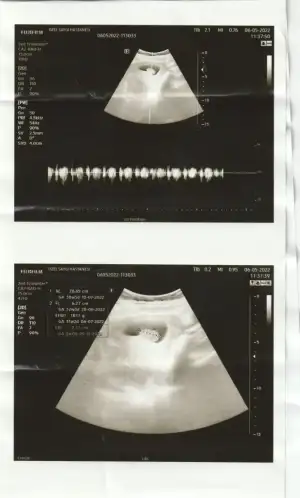

Canım benim de ultrason görüntüsü 6+3 bakabilir misin cinsiyet nedir şimdiden teşekkürler

• IMG20220427155428.webp

IMG20220427155428.webp

20,3 KB · Görüntüleme: 55